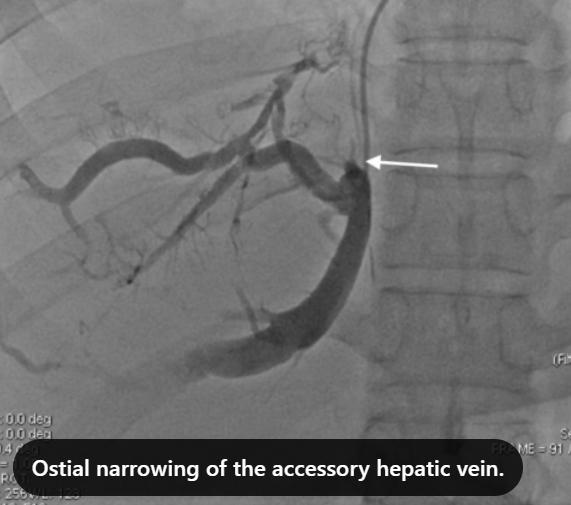

Clinical Case [Uncaptioned image] [Uncaptioned image]

Image Findings: The patient underwent contrast-enhanced computed tomography which showed features of a congested liver with flip-flop pattern of enhancement. Hepatic veins show hypoattenuation on delayed phase. An accessory hepatic vein is also noted in segment VI. A diagnosis of Budd Chiari syndrome (BCS) was made on the basis of the clinical and imaging features. The patient was referred to the interventional radiology team for an endovascular rescue. On conventional venogram, the diagnosis of BCS was confirmed as the hepatic veins were thrombosed. An accessory segment VI hepatic vein was noted draining into the IVC…

Title: Accessory right inferior hepatic vein [Uncaptioned image] [Uncaptioned image]

Discussion:Marked dilatation of the pulmonary trunk (6.7 cm) with the right (5.4 cm) and left (4 cm) main branches. Lung window shows mild bilateral diffuse faint groundglass centrilobular lung nodules that may reflect an underlying infection. Scans through the upper abdomen revealed average size cirrhotic liver and reflux of contrast into the IVC and hepatic veins with Incidental opacification of accessory right inferior hepatic vein…